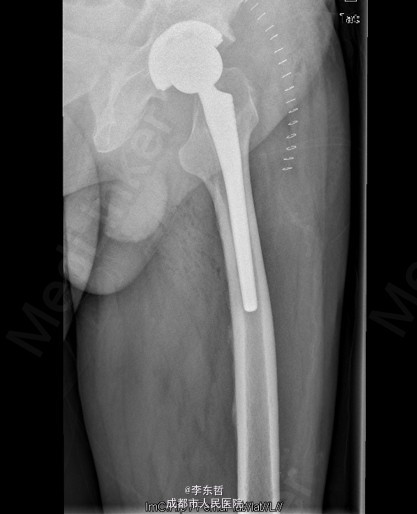

患者男,76岁,因“外伤致左髋部疼痛40多年,加重伴跛行2年”入院;患者自诉40多年前因一次摔伤致左髋关节脱位,给予手法复位后治愈,以后时有疼痛,关节活动好,不影响行走,4年前出现左髋部疼痛加重,活动后明显,休息后缓解,无腰腿痛,无肢体麻木等不适,给予对症治疗,稍有好转,以后反复发作,长时间行走后疼痛明显加重,2年前出现左下肢无力,长距离行走后出现跛行,且左髋关节有异响感;2月前出现左髋部疼痛加重,行走时尤为明显,步行约500米即出现疼痛,伴跛行,偶有静息痛;以后反复出现左髋部疼痛,并逐渐加重,严重影响日常生活;1月前于当地医院摄片提示左股骨头坏死,为求进一步治疗,遂来我院,门诊以“左髋骨关节炎”收入住院。 患者自患病以来精神、饮食、睡眠可,二便正常,体重无明显变化。

查体:左侧腹股沟中点深压痛,左髋部伴有轴向叩击痛,双下肢感觉正常,双足背动脉搏动良好。左下肢较右下肢短缩约2cm;左髋屈65°,伸0°,内收10°,外展20°,内旋5°,外旋10°,左髋活动受限,内外旋诱发疼痛;Thommas征阴性,“4”字试验阳性;左下肢肌力正常,活动良好,右侧正常 ;辅助检查:X片示:左侧股骨头塌陷、密度增高,股骨头坏死可能,左髋骨质疏松.。

初步诊断:左髋创伤性骨关节炎 诊疗计划:1、向患者及家属交待病情及注意事项。2、向上级医生汇报患者病情。3、完善血常规,心电图,肝肾功等检查,择期手术治疗。4、密切观察病情变化,根据病情及时处理。